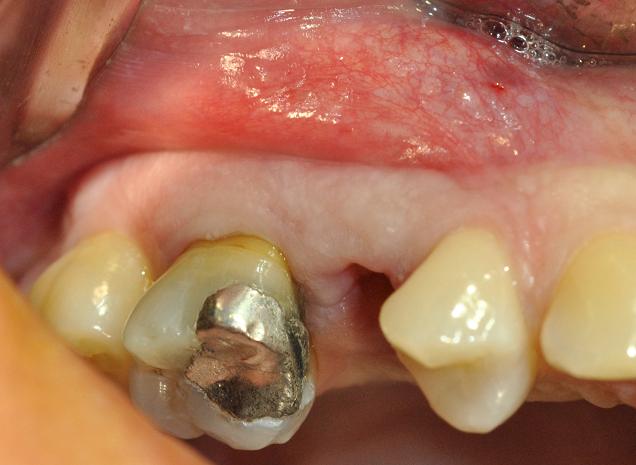

esame iniziale, 14gg dopo la rimozione del frammento coronale per consentire un'adeguata banda di tessuti molli

incisione trapezoidale in pèrevisione di procedure GBR